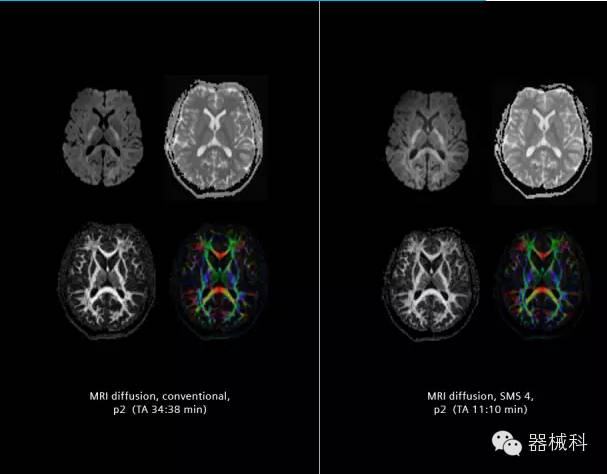

在2015年RSNA上,西門子隆重發(fā)布了Simultaneous Multi-slices 技術(shù)(即同時(shí)多層采集技術(shù),簡稱SMS),這是磁共振掃描技術(shù)中第一次引入“同時(shí)多層”的概念,此概念技術(shù)的發(fā)布,將對未來磁共振成像領(lǐng)域帶來巨大的變革!

SMS技術(shù)可以將原本用于科研的高級(jí)成像技術(shù)轉(zhuǎn)化成臨床常規(guī)。

擁有了SMS“同時(shí)多層”采集技術(shù)之后,用戶可以在非常短的時(shí)間內(nèi)完成MR掃描,結(jié)合西門子靜音技術(shù),大大提高患者的舒適性,或在單位時(shí)間內(nèi)采集更多的數(shù)據(jù),也可以得到高精度、高準(zhǔn)確性、大數(shù)量的功能成像數(shù)據(jù),為臨床和科研提供強(qiáng)大的支持。專家認(rèn)為,SMS“同時(shí)多層”采集技術(shù)未來在 提高成像質(zhì)量、外科手術(shù)計(jì)劃、降低術(shù)后神經(jīng)功能缺陷、提高fMRI的時(shí)間采集效率、提高靜息態(tài)功能磁共振數(shù)據(jù)質(zhì)量等方面將帶來深遠(yuǎn)影響,希望該技術(shù)可以盡早面世,引領(lǐng)磁共振進(jìn)入多層時(shí)代!